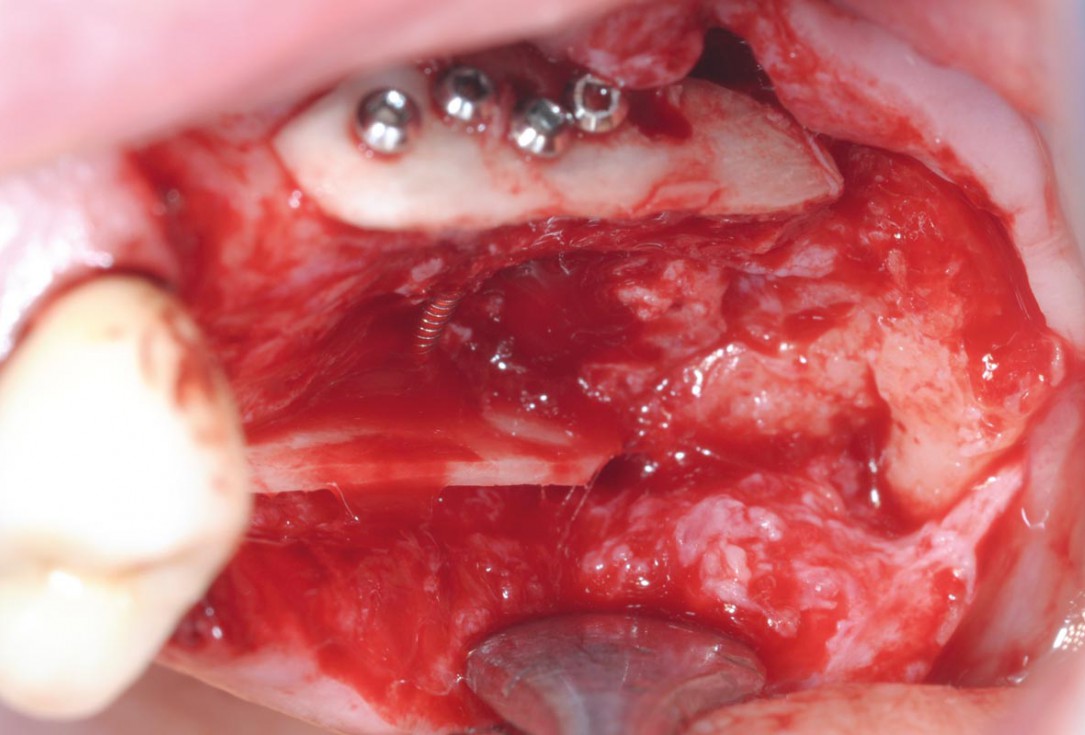

4/15 - Intraoperative view after fixation of maxgraft® cortico with a micro screw system. Placement in parallel technique to obtain a horizontal and vertical augmentationTreatment of a combined horizontal and vertical bone defect in the maxilla with maxgraft® cortico in the allogenic shell technique - Dr. R. Würdinger

5/15 - Filling of the container with maxgraft® cortico-cancellous granulesTreatment of a combined horizontal and vertical bone defect in the maxilla with maxgraft® cortico in the allogenic shell technique - Dr. R. Würdinger